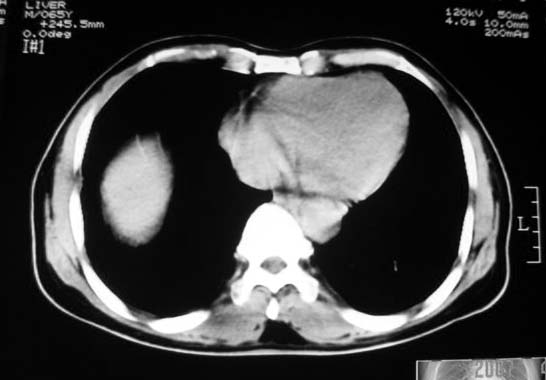

考虑胃的肿瘤或胰尾肿瘤,肝右叶后下段低密占位警惕转移。建议增强检查

从这些图像上看,此软组织团块影,在胃腔的外面,胃壁是一种受压的改变,所以考虑此病灶和胃没有关系,建议进一步增强ct检查。

能排除副脾吗?还是强化一下吧

病灶起源于胃壁向腔内外突出,边缘光整,内可见片状低密度区,考虑间质瘤可能性大,建议增强扫描。